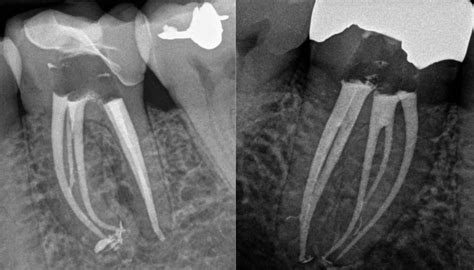

Root canal treatment is the most well-known endodontic procedure. It involves removing the infected or damaged pulp from the tooth, cleaning and disinfecting the inside of the tooth, and then filling and sealing it with a biocompatible material. This procedure is typically performed under local anesthesia to ensure the patient's comfort.

• Performing a clinical examination, including X-rays and other diagnostic tests

Filling and Sealing

Once the inside of the tooth has been thoroughly cleaned and disinfected, the dentist will fill and seal the tooth with a biocompatible material, such as gutta-percha. This material helps to prevent further infection and restore the tooth's structure.